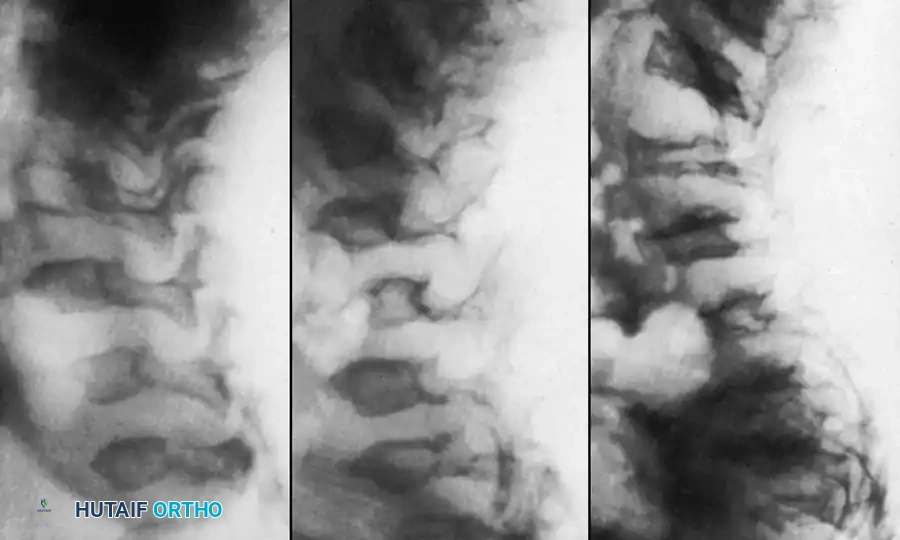

Fig. 38-219 A, Preoperative lateral radiograph of a pediatric patient with achondroplasia demonstrating severe, rigid thoracolumbar kyphosis.

Additional imaging demonstrating the complex osseous anatomy and pedicle morphology that must be navigated during instrumentation in skeletal dysplasias.